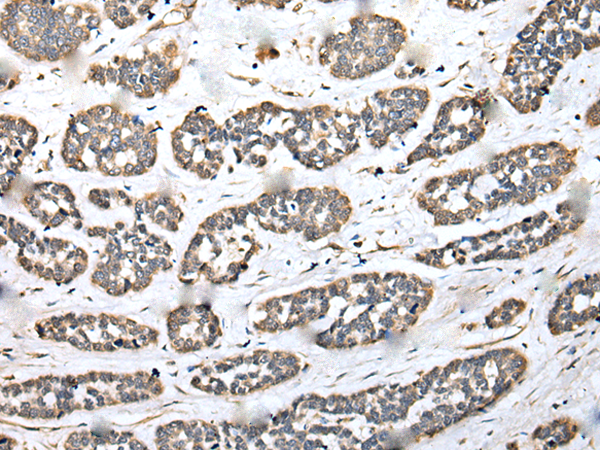

Name of antibody: |

DENR |

Synthetic peptide of human DENR |

density regulated re-initiation and release factor |

WB Positive control: |